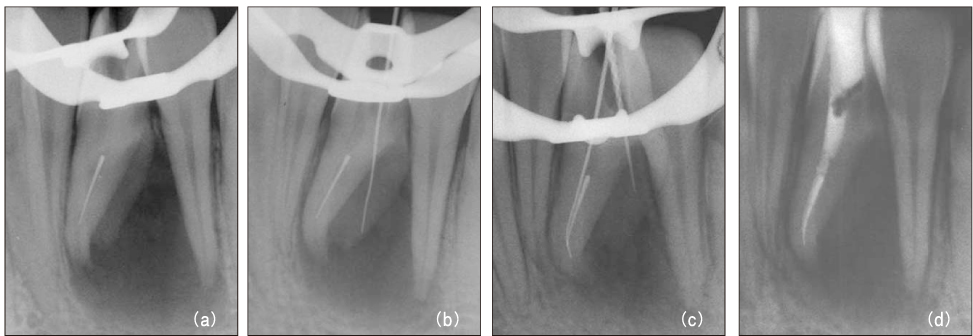

Figure 11

Diagnostic intraoral radiograph (a). By-passing with hand file (b) and canal obturation (c, d). 30-month recall (e): tooth is symptomless.

Figure 11 Diagnostic intraoral radiograph (a). By-passing with hand file (b) and canal obturation (c, d). 30-month recall (e): tooth is symptomless.